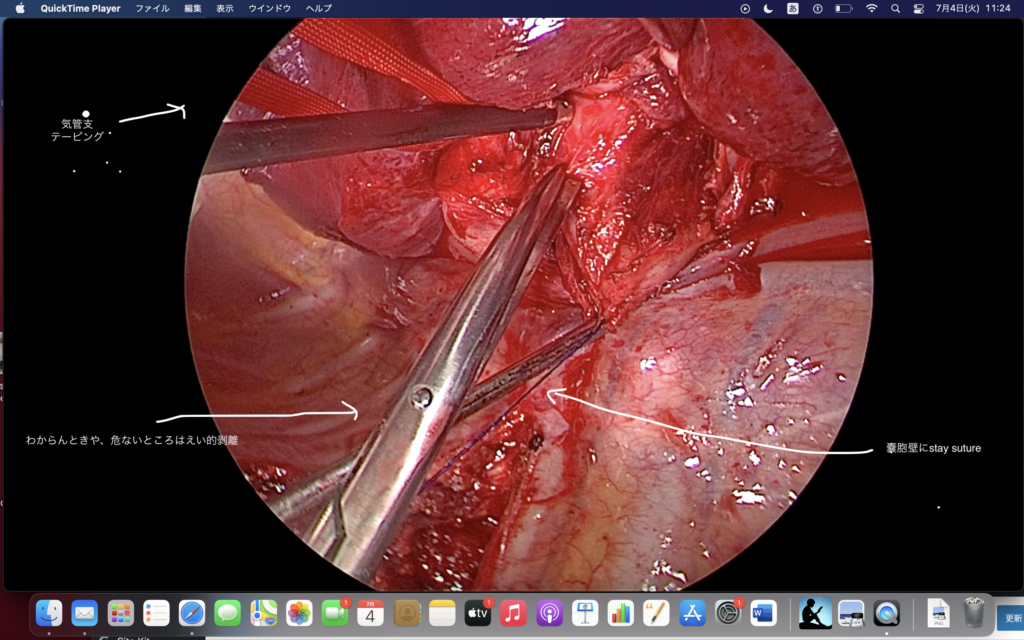

「知っているものを出していく」ことが重要になる。

それを如何(どう)達成するか。

前の手術の復習、気管支動脈の姿はどんな?

ステイスーチャーはzでかけたら良い。

3者(A, B, V)との関係をつねに意識してください。

直角使うときも、ぶすっとはやらないよ!

自然に通るところは通して切ってもいいけど。

膜と胸壁でむすびつけると、一本手が節約できる。